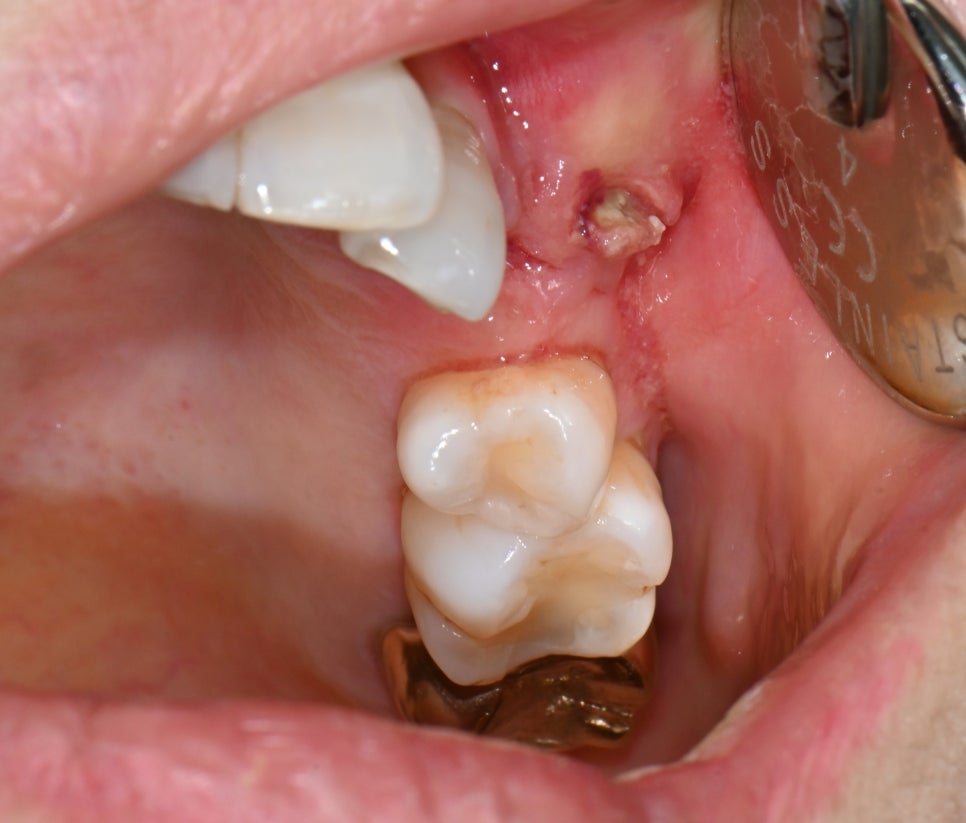

👀 내원 당시 모습

📸 초진 사진

환자분은 타 치과에서 발치 후 염증이 생겨

잇몸이 부어오르고 고름이 반복적으로 생기는 상태였어요.

골수염(Osteomyelitis) 환자분 초진 정면 사진

📸

좀 더 자세히 촬영한 사진입니다. 눈으로 확인했을 때 **잇몸 안쪽 으로 고름 덩어리가 있었고,

진단명은 ‘골수염(Osteomyelitis)’.

즉, 염증이 단순한 표면이 아니라 뼛속까지 퍼진 상태였어요.

골수염(Osteomyelitis) 환자분 초진 구강 사진